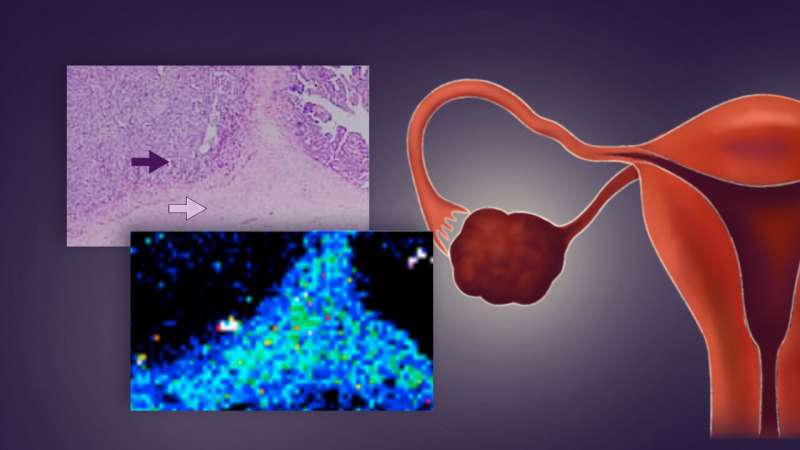

The team looked at the amount of platinum in both the tumor itself and in its stroma, which is the part of the tumor that supplies cancer cells with nutrition and gets rid of waste products. They found that there were two basic types of platinum distribution: one where the platinum was evenly distributed throughout both the tumor itself and the stroma, and one where the platinum was mostly in the stroma.

The difference was staggering: only one of the 11 patients with an even distribution of platinum died in the three years after diagnosis, whereas half of 16 patients with most of the platinum in the stroma were dead within three years. In addition, the patients with tumors that showed an even distribution of platinum were also less likely to develop a tumor that was resistant to further treatment.

“We showed that there were two different patterns of platinum distribution within the tumor tissue. The difference in the distribution was shown to be significantly correlated with prognosis, suggesting that it is possible to discriminate between platinum-resistant and platinum-sensitive tumors before they recur,” explains Kajiyama. “Using this method, early diagnosis of platinum resistance and selection of appropriate postoperative anticancer therapy for patients as well as a new ovarian cancer treatment strategy are possibilities.”